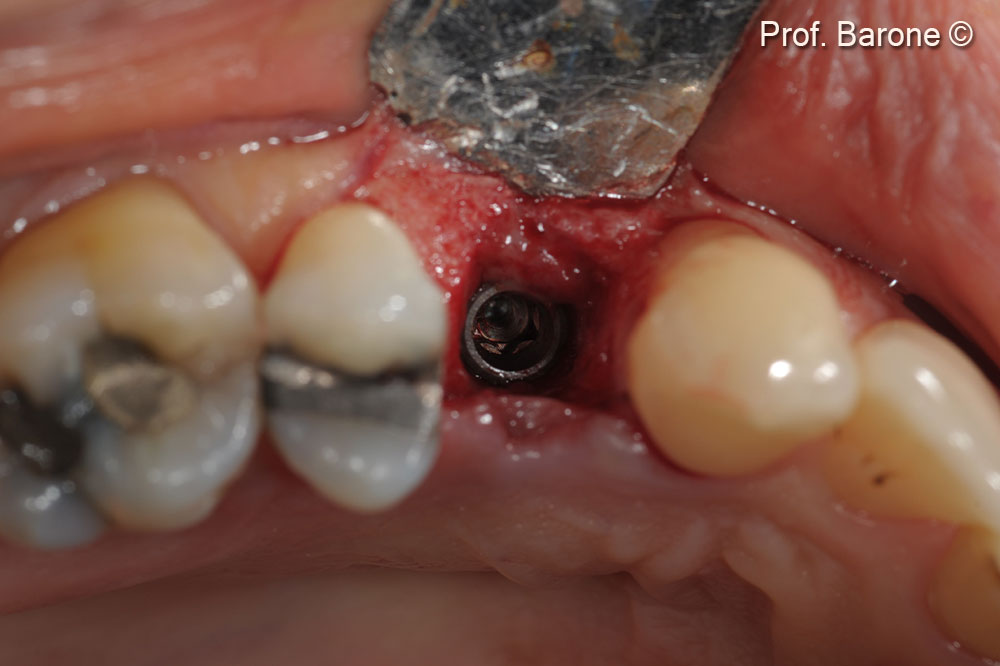

Clinical occlusal view during implant site preparation